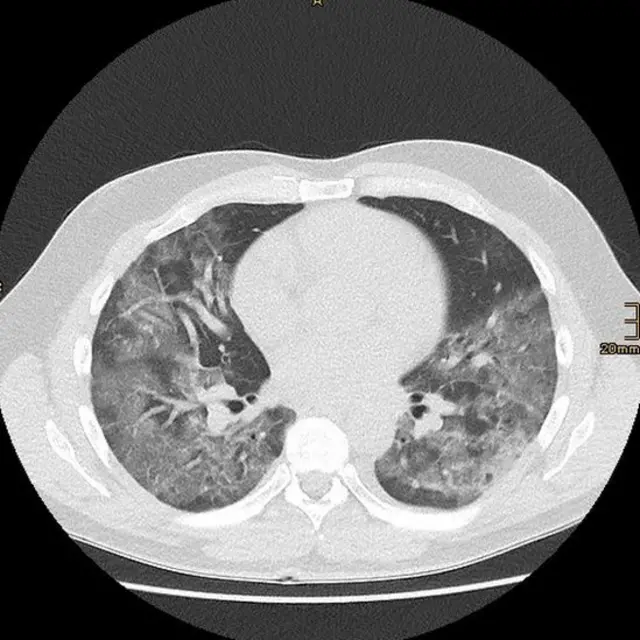

La ciencia detrás de esta temprana lección está emergiendo ahora, con un estudio de Wuhan, China, que describe los cambios patológicos del pulmón en las tomografías de pacientes completamente asintomáticos.

Los investigadores encontraron lesiones consistentes con inflamación del tejido pulmonar subyacente (opacidades de vidrio esmerilado y consolidación, para usar la jerga médica), que no son específicas a la infección de SARS-CoV-2 y pueden verse en muchas otras enfermedades pulmonares.

Lo que sigue siendo un misterio es por qué, a pesar de estos cambios, los pacientes no muestran síntomas típicos de neumonía, como falta de aire severa.

El estudio refuerza que la ausencia de síntomas no implica la ausencia de daño.

Las lesiones en una tomografía determinan qué tratamiento se necesita. Todavía hace falta una decisión personalizada basada en el juicio clínico.